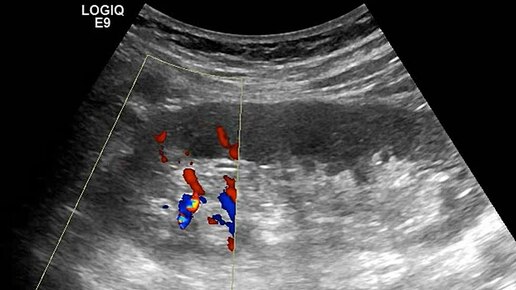

Ультразвуковые находки от врача УЗД Зорина Я.П.